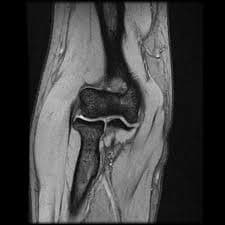

Protect your freedom of movement with a Knee MRI! Fast and accurate diagnosis thanks to our modern medical imaging center. Click for radiology services and check-up packages!